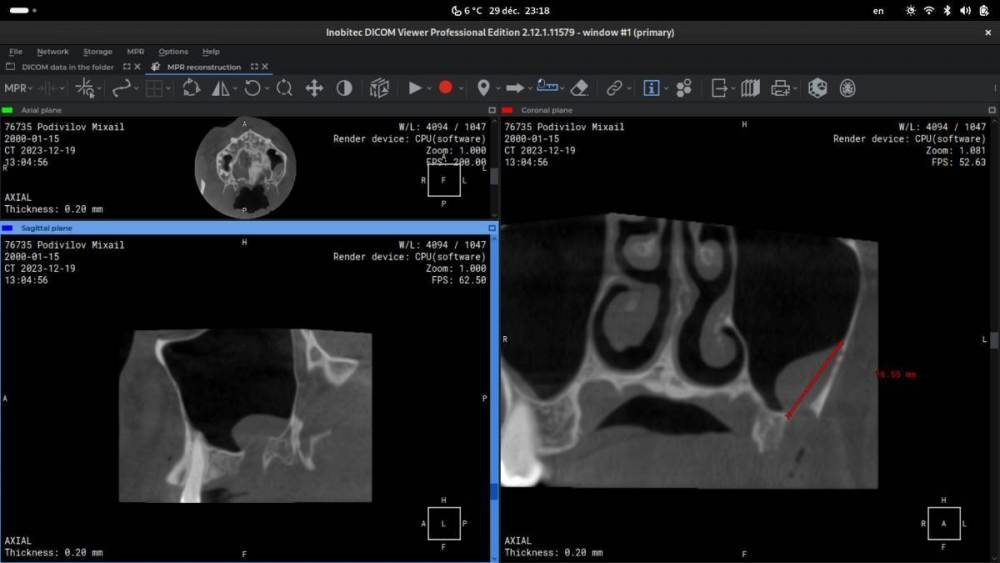

Сделал КТ и посетил хирурга, который удалял мне зуб. Врач сказал, что перфорации гайморовой пазухи нет и назначил противовоспалительные таблетки. Лучше, к сожалению, не стало: а сегодня так вообще отмечаю, что ныть стало гораздо сильнее.

Честно говоря, руки опускаются и это очень сильно бьёт по продуктивности. Сложно на чём-либо концентрироваться и чем-либо заниматься в принципе. Постоянная боль очень психологически выматывает. На первой фотографии панорамные снимки (до депульпации, после депульпации и после удаления зуба). На второй — КТ.

На КТ я вижу какое-то образование — видимо, киста. Ну, явно какое-то воспаление. Но вот, что интересно: сегодня я разглядел на панорамных снимках то же самое образование, то же самое воспаление! То есть, вероятно, тот зуб вовсе не нужно было удалять. Я связывал появление этой кисты с удалением зуба, но, видимо, оно было и до этого.

Здравствуйте, киста в пазухе невоспалительной природы, с высокой долей вероятности существовала задолго до появления симптомов. Думаю, имеет смысл обратиться к неврологу. Вряд ли это связано с зубами и пазухой.